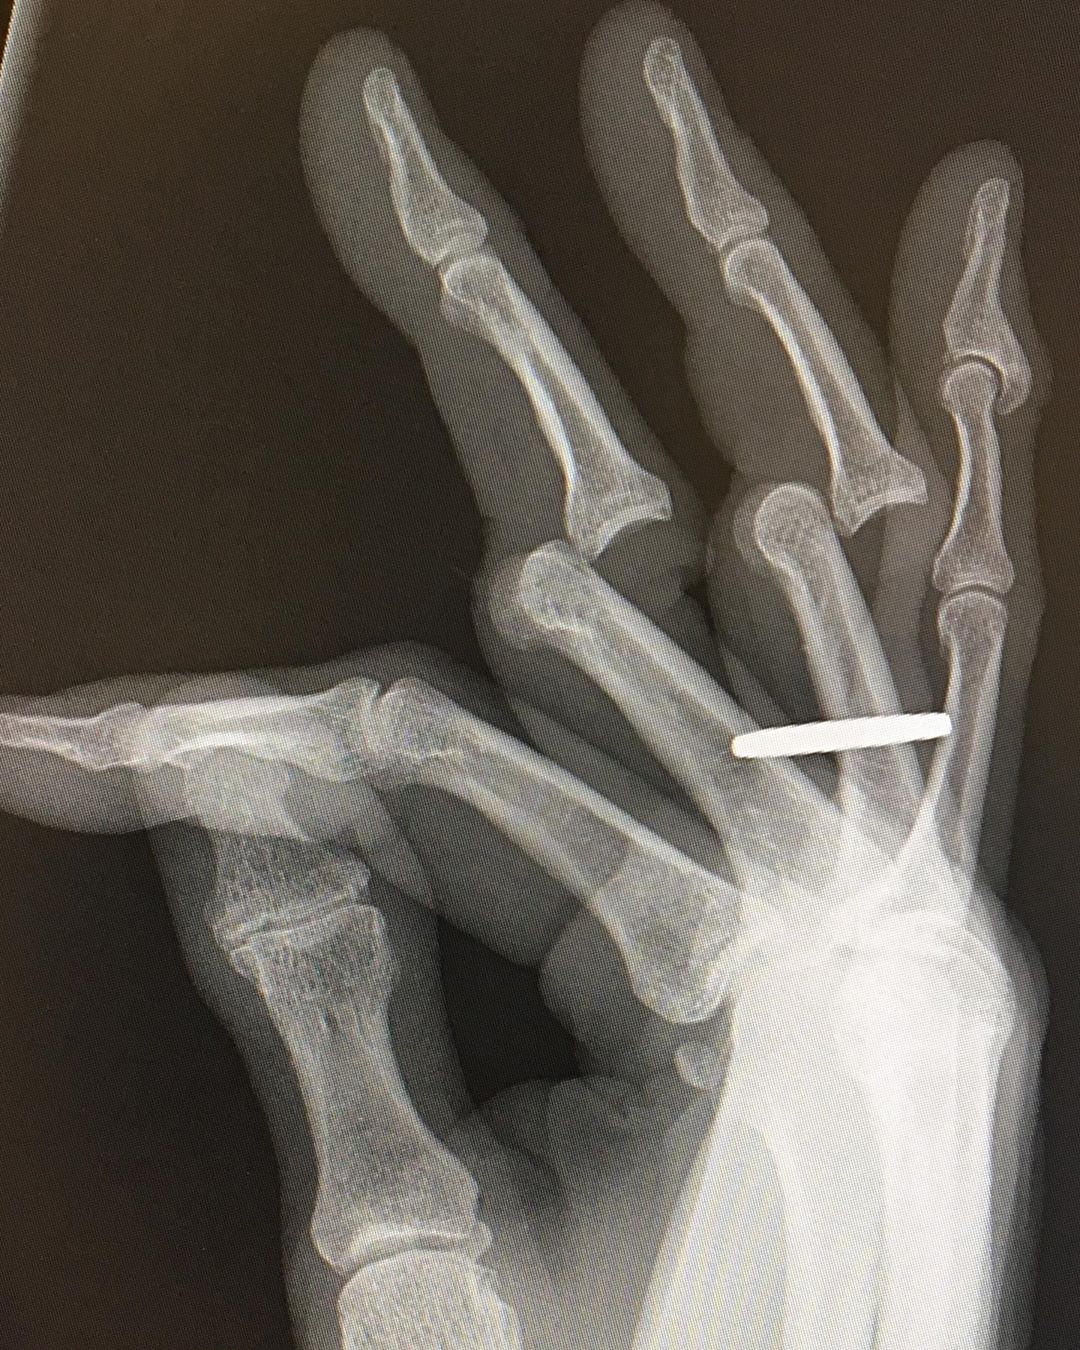

Hawk, tuvo que ir de urgencias a un centro médico para que le revisaran sus dedos fracturados y mostró las impactantes imágenes:

“Acabo de recibir mis radiografías. Tuvieron que cortarme el anillo antes de devolver mis huesos a su posición vertical. Todavía mis dedos están adoloridos, rígidos e hinchados, pero los puedo usar. Y todavía amo mi trabajo “.

Aquí las impactante imágenes: